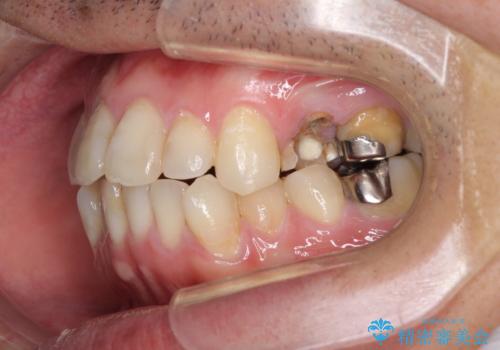

ボロボロとなっていた歯は抜歯が必要な状態でしたが、舌側転位している歯を移動させることで抜歯スペースを埋めることができるため、矯正治療により歯列を整えることとしました。

矯正治療後には抜歯が必要な歯に隣接してむし歯となっていた歯をオールセラミッククラウンにて補綴治療を行うこととしました。

矯正治療開始時に、インビザライン矯正の加速装置を購入されましたが、インビザライン自体をあまりしっかりと使用できず、4年間の治療期間となりました。